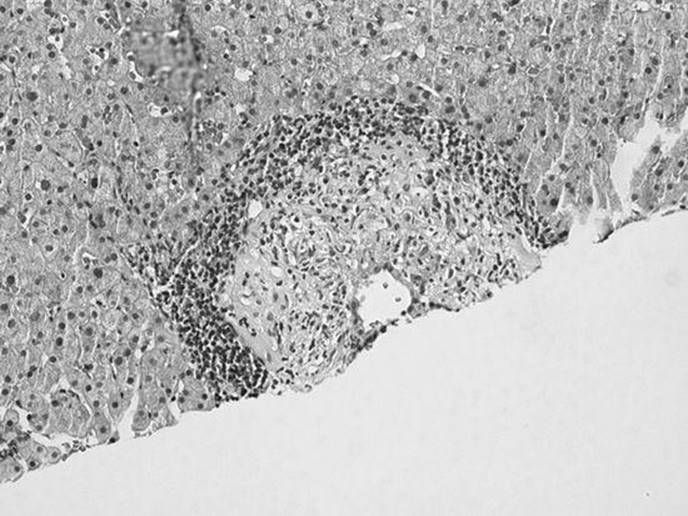

The liver biopsy specimen shown in the figure below is described in the pathology report as having nodular lymphocytic portal infiltrates, some with germinal centers. This is most suggestive of what type of viral hepatitis?

Figure 51-4

Hepatitis C. The presence of a portal area with a lymphoid aggregate or a follicle with a germinal center in a liver specimen with other features of chronic hepatitis is most suggestive of chronic hepatitis C. It should be noted that hepatitis C is notable for sometimes having some degree of bile duct involvement/injury. This can make the distinction between recurrent hepatitis C and allograft rejection difficult in some liver transplant biopsies.